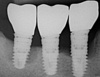

Cette patiente de 60 ans bénéficie d’implants à la mandibule depuis plus de 20 ans et elle présente un métabolisme osseux défavorable. Au cours d’une maintenance implantaire, une péri-implantite a été identifiée sur le premier et le dernier de ces trois implants.

Après un assainissement implantaire et un suivi régulier, la péri-implantite a disparu et la patiente va profiter encore longtemps de ses implants.